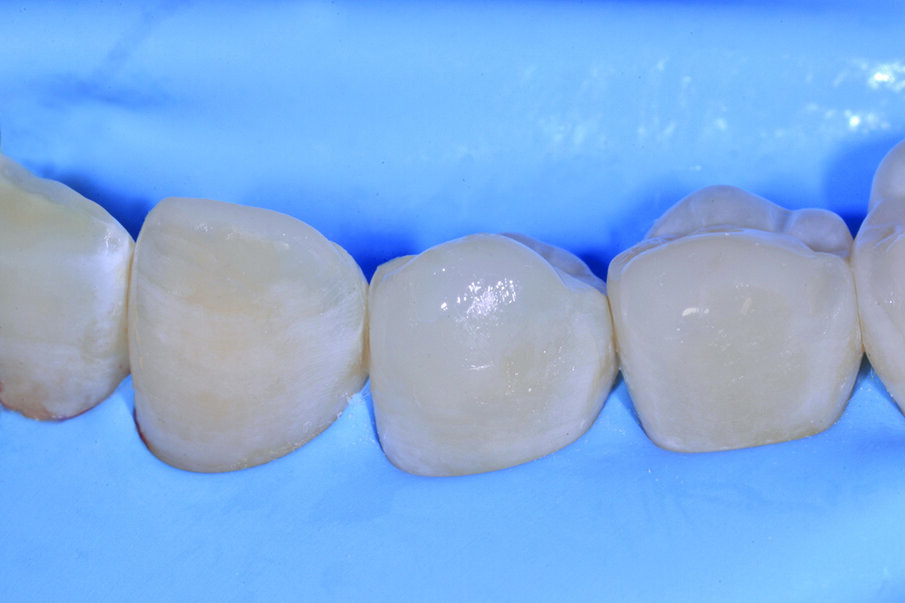

Fig. 1a_Caso iniziale: il paziente presenta perdita di dimensione verticale a causa di erosioni e abrasioni.

Figg. 6-9_Le superfici occlusali erose e/o abrase vengono ricostruite con strati sottili di smalto composito Enamel Plus HRi Bio Function.